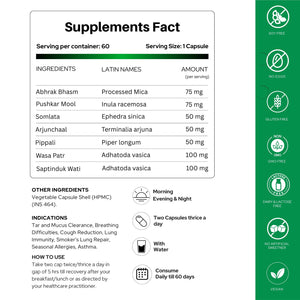

खुराक और उपयोग

उपयोग विधि: पूर्णतः ठीक होने तक, या अपने चिकित्सक के निर्देशानुसार, नाश्ते/दोपहर के भोजन के बाद, दिन में दो या तीन बार (प्रत्येक 5 घंटे में) दो कैप्सूल लें।- सावधानी: यदि आप गर्भवती हैं, स्तनपान करा रही हैं, या श्वसन संबंधी दवाइयां ले रही हैं तो अपने चिकित्सक से परामर्श करें (कुछ जड़ी-बूटियां परस्पर क्रिया कर सकती हैं या प्रतिरक्षा को प्रभावित कर सकती हैं)।

मुख्य सामग्री

- भृंगराज (एक्लिप्टा अल्बा): फेफड़ों की सूजन को कम करता है, बलगम को साफ करता है, फेफड़ों के ऊतकों की रक्षा करता है।

- मुलेठी (ग्लाइसीर्रिजा ग्लबरा): कफ निस्सारक; बलगम को ढीला करता है, श्वास नलिका को आराम देता है, खांसी को कम करता है।

- कांत लौह (लौह आधारित कैल्क्स): रक्त ऑक्सीजन का समर्थन करता है, ऊतक मरम्मत में सहायता करता है।

- आवला (एम्ब्लिका ऑफिसिनेलिस): एंटीऑक्सीडेंट; प्रतिरक्षा को बढ़ाता है, विषाक्त पदार्थों को कम करता है।

- कपर्द भस्म (कौड़ी के खोल का छिलका): वायुमार्ग को मजबूत करता है, बलगम को साफ करता है, जलन को कम करता है।

- गिलोय (टीनोस्पोरा कॉर्डीफोलिया): एडाप्टोजेन; प्रतिरक्षा को बढ़ाता है, फेफड़ों को शुद्ध करता है, संक्रमण को कम करता है।

नीम (एजाडिरेक्टा इंडिका): रोगाणुरोधी, एलर्जीरोधी; संक्रमण को दूर करता है, एलर्जी को कम करता है।- तुलसी (ओसीमम सैंक्टम): कफ निस्सारक; कफ को साफ करती है, खांसी को शांत करती है, फेफड़ों के स्वास्थ्य को बढ़ाती है।

- सप्तपर्ण (एल्सटोनिया स्कॉलरिस): रक्त शुद्ध करता है, रक्तसंकुलता कम करता है, श्वसन क्रिया में सहायता करता है।